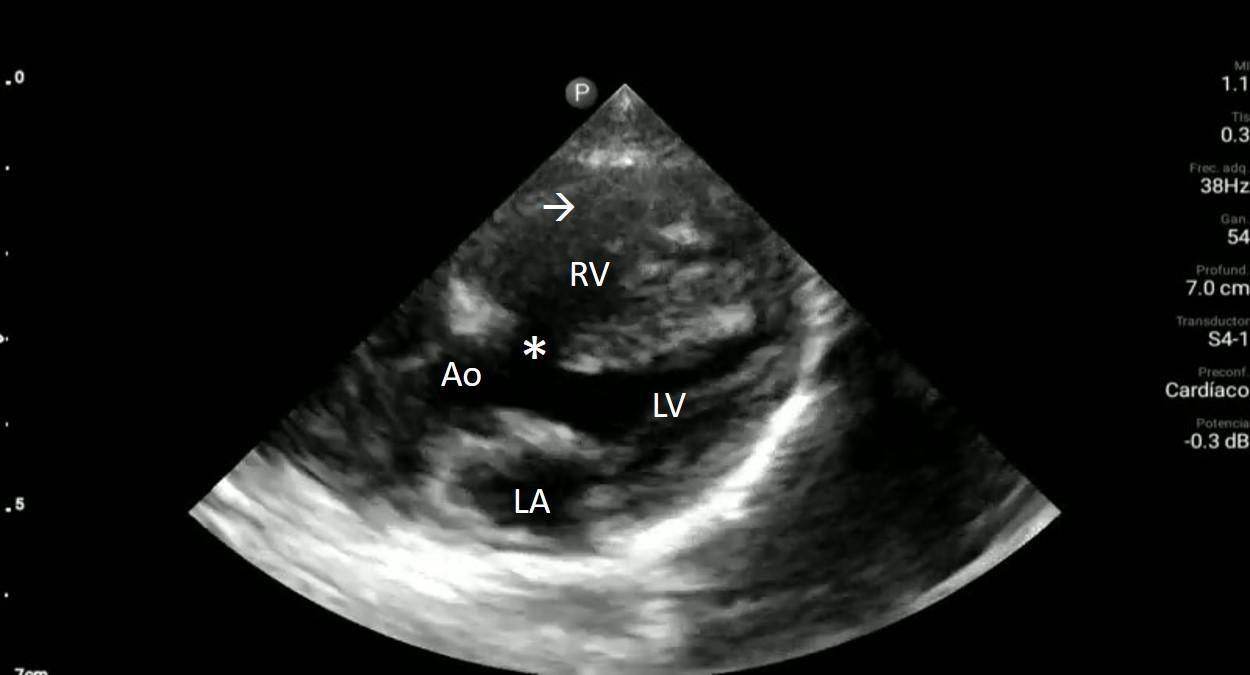

Upon closer inspection, parasternal long-axis view revealed a ventricular septal defect with an overriding aorta and RVH concerning for TOF (Image 2). Parasternal shortaxis cardiac view redemonstrated RVH with interventricular septal flattening indicative of right ventricular pressure

overload from RVOT obstruction (Image 3). Pulmonary ultrasound revealed a normal A-line pattern, and POCUS

Image 2. Parasternal long-axis view of the heart highlighting the findings of a ventricular septal defect (*) with an overriding aorta (Ao) and right ventricular hypertrophy (arrow). LA indicates left atrium; LV, left ventricle; RV, right ventricle.

Treatment was shifted from a focus on sepsis to TOF management. Additional IVF hydration was limited, and the patient was started on propanolol for rate control. Due to the patient’s age, the decision was made to not administer prostaglandins as he was likely not ductus dependent. He was found to improve after these interventions. Cardiology was consulted, and despite not identifying physical exam findings concerning for TOF such as skin discoloration signifying cyanosis, or a systolic thrill and ejection murmur at the left sternal border, once they were shown the POCUS images cardiology consult initiated procedures for referral to the National Institute of Cardiovascular Diseases in Lima for definitive surgical treatment. Four days later a comprehensive echocardiogram confirmed the diagnosis of TOF.

Image 3. Parasternal short-axis view of the heart notable for interventricular septal flattening (*) due to right ventricular pressure overload in the setting of right ventricular hypertrophy (arrow). LV, left ventricle; RV, right ventricle.

Video 1. Parasternal long-axis view of the heart. Ventricular septal defect (*); overriding aorta (Ao); right ventricular hypertrophy (arrow); left atrium (LA); left ventricle (LV) right ventricle (RV).

Video 2. Interventricular septal flattening due to right ventricular pressure overload (*); right ventricular hypertrophy (arrow); left ventricle (LV) right ventricle (RV).